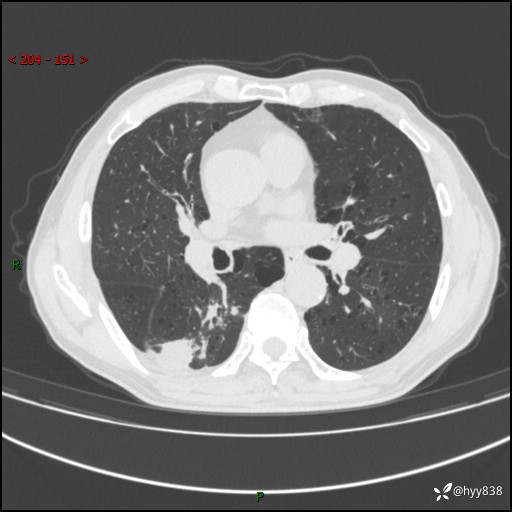

老年男性,发现右下肺结节3天。结节+卫星灶,似曾相识---结果公布~

主诉:发现右下肺结节3天

简要病史:患者3天前于我院常规体检时行胸部CT提示“右下肺结节35mm*24mm”,自觉无发热、咳嗽、咳痰,无胸痛、咯血、气促加重,无声嘶、吞咽困难,无乏力、盗汗、体重减轻等不适。为求进一步诊治,入我院求诊,门诊以“右下肺结节待查”收入我科。患者3天前于我院常规体检时行胸部CT提示“右下肺结节35mm*24mm”,自觉无发热、咳嗽、咳痰,无胸痛、咯血、气促加重,无声嘶、吞咽困难,无乏力、盗汗、体重减轻等不适。为求进一步诊治,入我院求诊,门诊以“右下肺结节待查”收入我科。 起病以来,患者精神、食欲、睡眠可,体力稍差,大小便正常,体重无明显变化。

辅助检查:CT

临床诊断:肺结节

胸部CT平扫